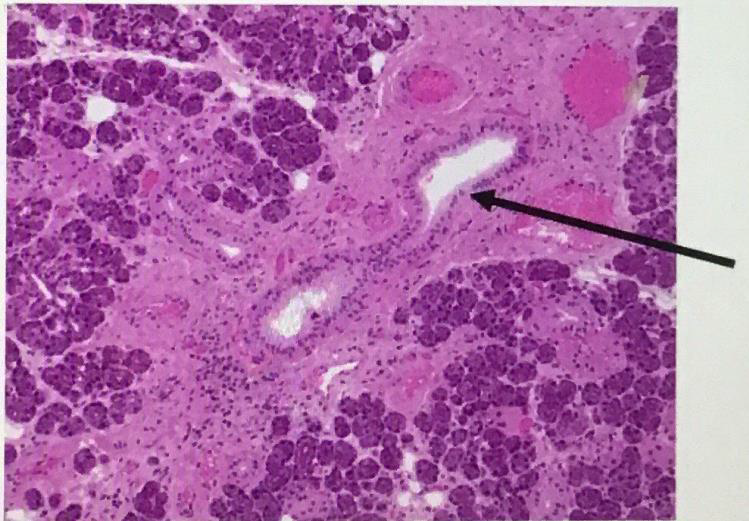

Sublingual gland

Parotid gland

Submandibular gland

Serous demilune

myoepithelial cell

intercalated duct

striated duct

Excretory duct

pseudostratified columnar epithelium